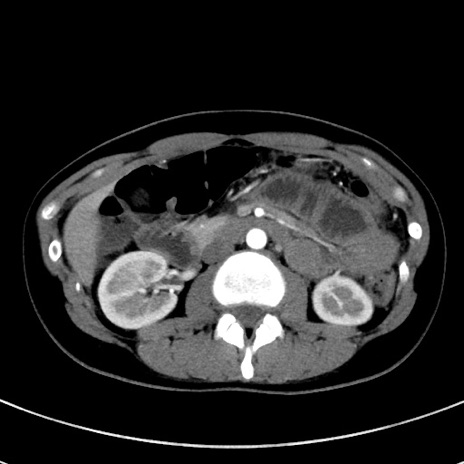

症例17(横断像)

【症例】20歳代女性

【主訴】嘔吐、下腹部痛

【現病歴】昨日夕食後に嘔吐し下腹部痛が出現。本日になっても嘔吐持続し改善しないため来院。

【身体所見】意識清明、BT 37.2℃、BP 108/67mmHg、腹部:平坦、やや硬、下腹部正中から右にかけて圧痛あり、反跳痛軽度あり、tapping pain(+)。

【データ】WBC 13600、CRP 14.94